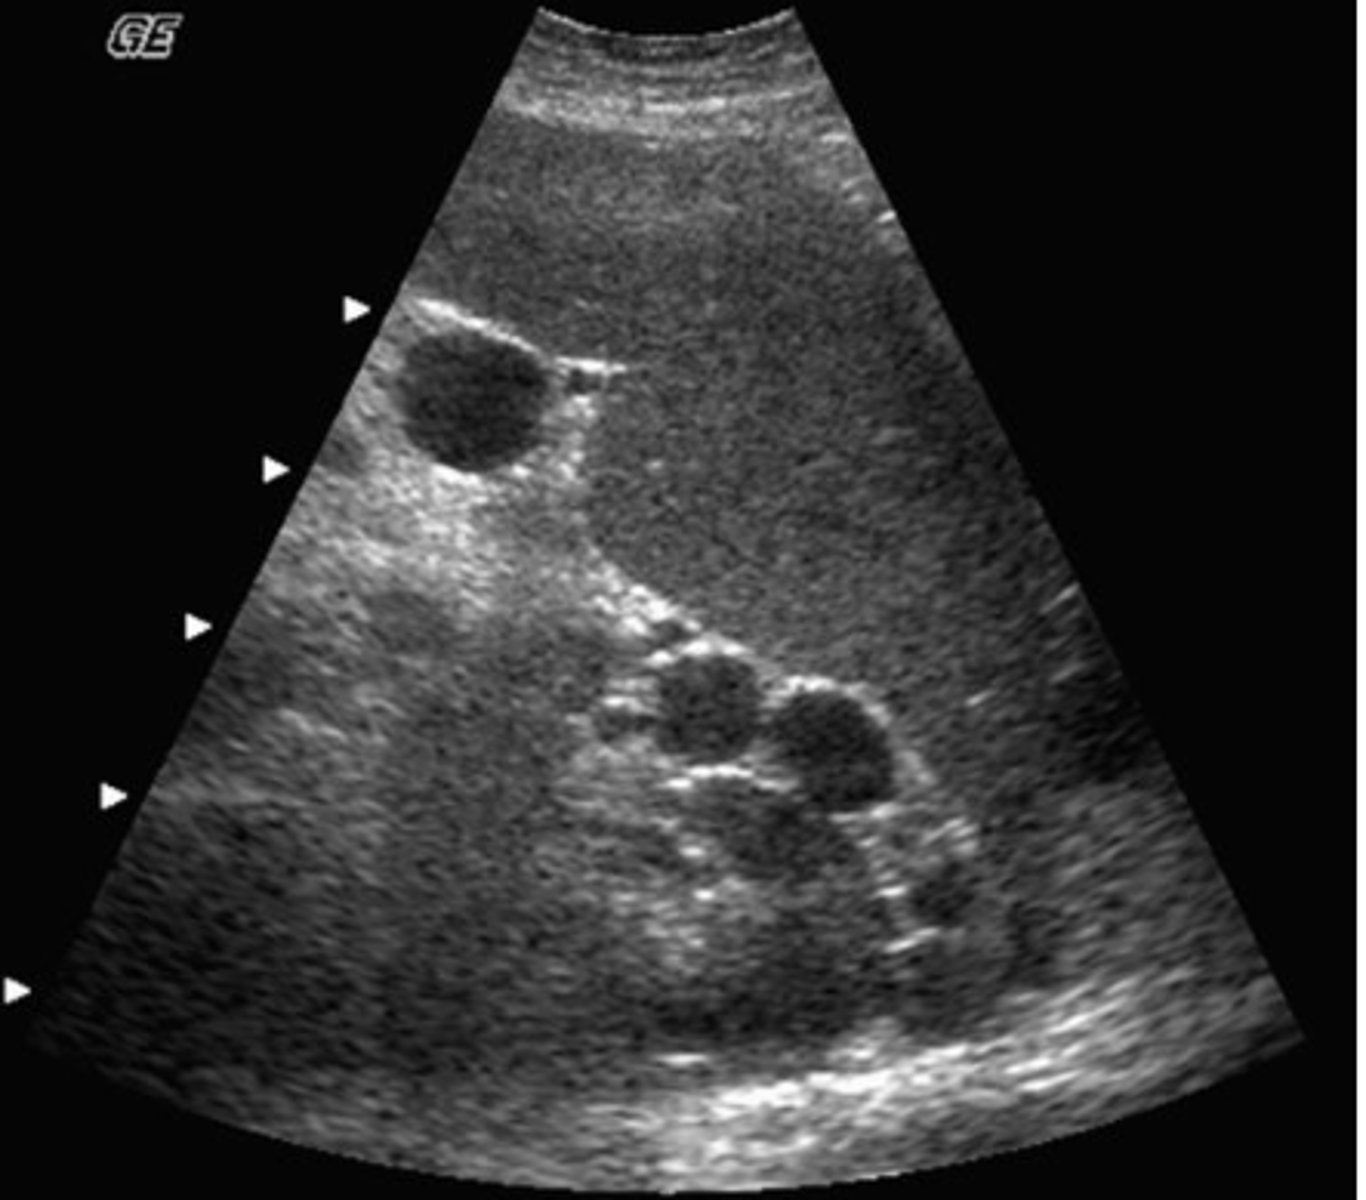

c. search for the presence of portosystemic collaterals

You are performing an ultrasound exam in a patient with a history of alcoholic liver cirrhosis. You have documented the presence of splenomegaly and dilated veins at the splenic hilum. Considering the patient's history and findings, what else should you look for?

a. search for signs of acute cholecystitis

b. carefully scan the spleen for presence of infarcts

d. check the pelvis for a left side mass

e. rule out the presence of an aortic aneurysm